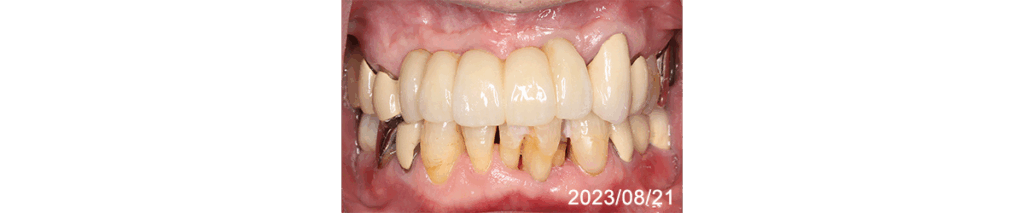

下顎に広範囲のインプラント治療が施され快適に過ごされていたので、上顎前方部の歯質劣化により残存歯でのブリッジが不能のためインプラント修復をご希望

義歯を使われることなく12年使用され、90歳手前で急に衰えられご逝去されました。